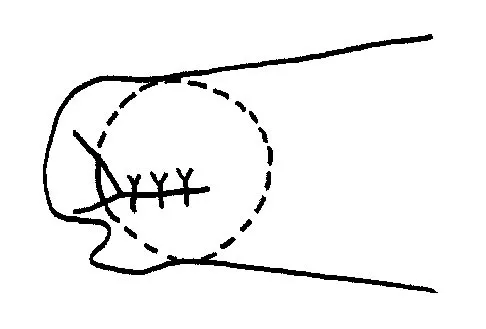

A 22-year-old skier reports painful range of motion in the left thumb after falling forward on his outstretched hand while holding his ski pole. Examination of the left thumb reveals increased AP laxity and 45 degrees of valgus laxity at the metacarpophalangeal (MCP) joint. Examination of the right thumb shows 25 degrees of valgus laxity at the MCP joint. Radiographs are normal. Management should consist of

Explanation